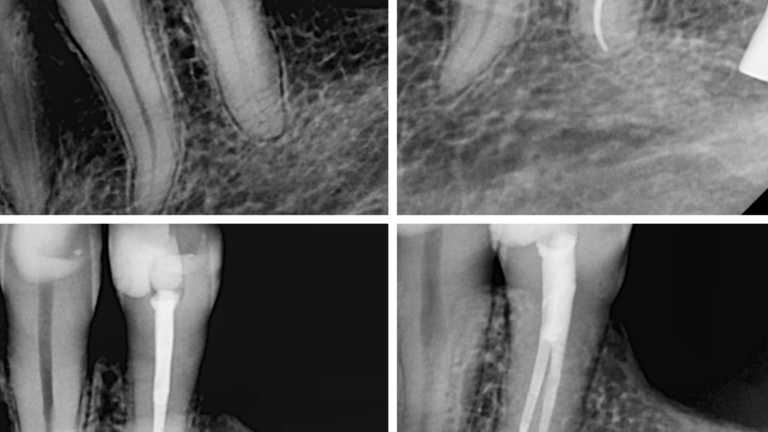

Caso clínico del doctor Marc Llaquet de una reendodoncia del diente 2.4 instrumentado con las limas RetreatAll® para…